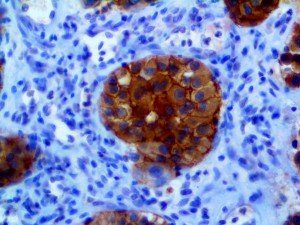

It is the ICU physician who is most likely to witness one of the deadliest manifestations of the abnormal immunological response, the cytokine storm syndrome (CSS). This response is also referred to by some as the cytokine release syndrome (CRS). CSS is characterized by continuous activation and expansion of macrophage and lymphocyte populations, which secrete large amounts of cytokines, causing the cytokine storm. This massive cytokine release is akin to hemophagocytic lymphohistiocytosis (HLH) disease, a syndrome characterized by initial unchecked and persistent activation of cytotoxic T lymphocytes and NK cells.

Clinical and laboratory manifestations of HLH include fever, enlarged liver and/or spleen, neurologic dysfunction, coagulopathy, liver dysfunction, cytopenias (i.e., low levels of erythrocytes, leukocytes, and/or platelets), hypertriglyceridemia, hyperferritinemia, hemophagocytosis, and eventually diminished NK cell activity as the immune system becomes progressively paralyzed. HLH can be familial (primary HLH) or secondary to another disease process (sHLH), such as rheumatic disease, in which it is referred to as macrophage activation syndrome (MAS, characterized by elevated ferritin).